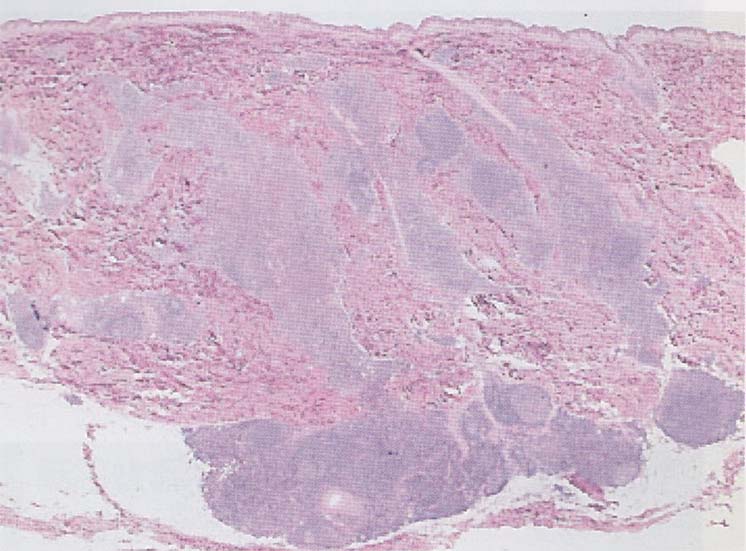

Nodular dermatitis

Superficial またはSuperficial and deep perivascular dermatitisのうち, 血管周囲の細胞浸潤が強く, 結節状のひろがりをみせるもの.

leukocyteclastic vasculitis, small vessel typeの中に結節状の細胞浸潤を伴うものがあるので,以下の2種類に分類するのがよいかもしれない.

結節状の細胞浸潤がある場合, つぎの鑑別ステップは, 浸潤細胞の種類に注目する.